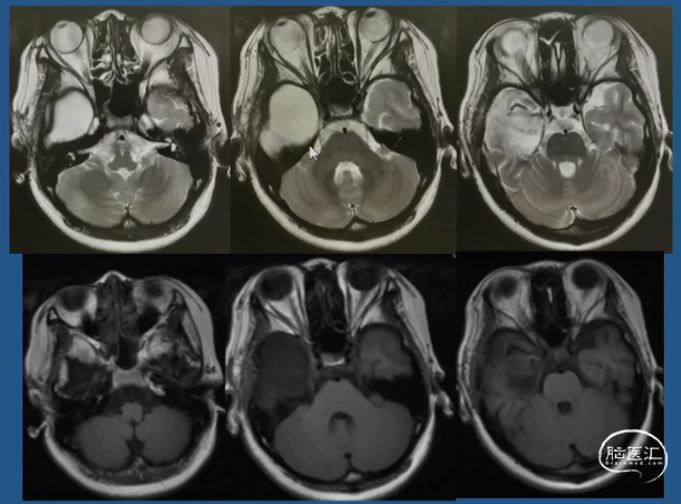

影像学表现:2018-03-05 MRI 常规MRI阴性

术后影像